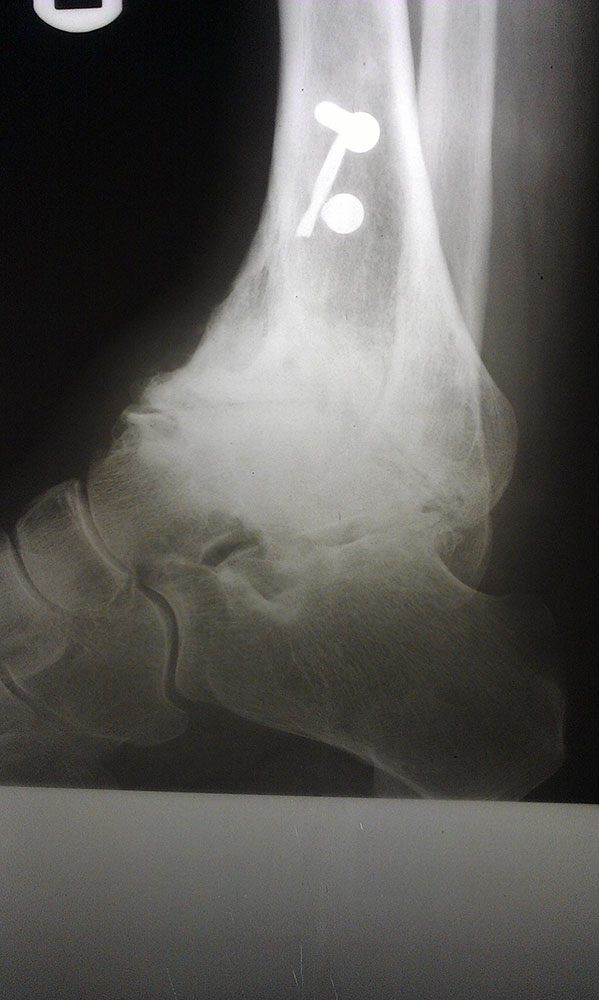

"Surgical misadventure" by another surgeon about 8 years ago. The wrong fixation was used for a flatfoot repair, & the deformity was not corrected. Patient came in with severe foot & ankle pain, with no arch at all. She was unable to play with her grandchild because the pain was so bad, & because she felt unsteady. The old hardware was removed, a lateral calcaneal lengthening osteotomy was performed along with a medial column/1st ray realignment. The ankle was painfully arthritic, & patient elected a total ankle replacement vs. an ankle fusion. She is now able to walk pain free & play with her grandchildren!